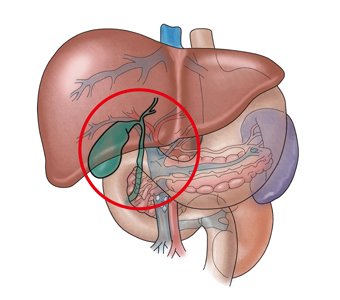

석회화 담낭이란 주머니처럼 말랑말랑해야 하는 담낭이 만성 담낭염 때문에 담낭 벽에 칼슘이 침착되면서 도자기처럼 석회화된 것을 의미합니다. 비교적 드물게 발생하는 질환입니다.

석회화 담낭이 발생하는 원인의 95% 이상은 담석에 의해 발생한 담낭의 만성적인 자극, 염증, 담석에 의한 담낭관의 폐쇄, 담석에 의한 담낭 벽의 출혈성 상처 등입니다. 50대 중반의 여성에게 잘 발견됩니다. 여성의 발생률이 남성보다 5배 정도 높습니다.

단순 복부 촬영(X-ray)에서 우상복부 담낭 내의 선상 혹은 점상(punctate)이 크게 석회화된 상태가 관찰됩니다. 복부 초음파와 복부 CT, MRI를 시행할 수 있습니다. 담낭암과 같은 악성 질환과 감별해야 합니다.